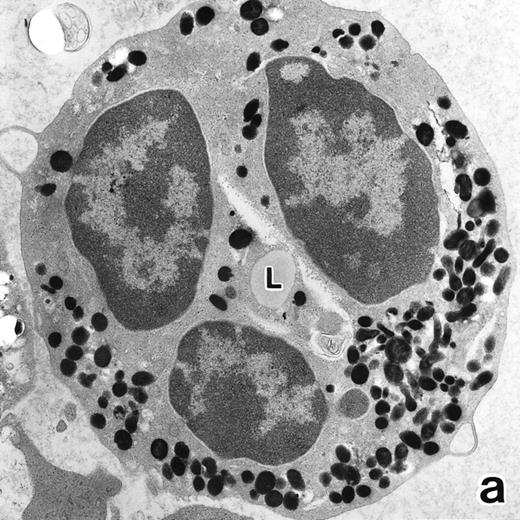

(a) A PMN that emerged in the APL cell culture of patient no. 3 in the presence of ATRA for 1 week. From the lobulated nuclear configurations and condensed heterochromatin, this cell looks like a PMN. However, the cytoplasm contains many MPO-positive primary granules but no secondary granules. (MPO-stained section, original magnification × 14,900.) (b) Higher magnification of a portion of the cell in (a), showing that the cytoplasmic granules are all MPO-positive. (MPO-stained section, original magnification × 30,100.)

APL cells in culture.APL cells in patient no. 3 were cultured in the presence of ATRA or G-CSF for 7 days, and their morphological changes were examined under a light microscope. After 5 days of culture with ATRA the cells displayed a tendency toward maturation, including nuclear lobulation, chromatin condensation, and a decrease or disappearance of azurophil granules, similar to that observed in bone marrow cells. The cells cultured with G-CSF for 7 days, on the other hand, retained a promyelocytic appearance with numerous azurophil granules that even seemed to have increased in size and/or number (data not shown). Electron microscopic examination showed the nuclei of the cells cultured with ATRA to be irregularly lobulated with marginally condensed heterochromatin and the lobulated nuclei to be often connected by nuclear filamentous structures, in a manner similar to the cells seen in the bone marrow (Fig 8). These cells contained numerous MPO-positive primary granules, including irregularly shaped granules, but no MPO-negative specific granules were identified.